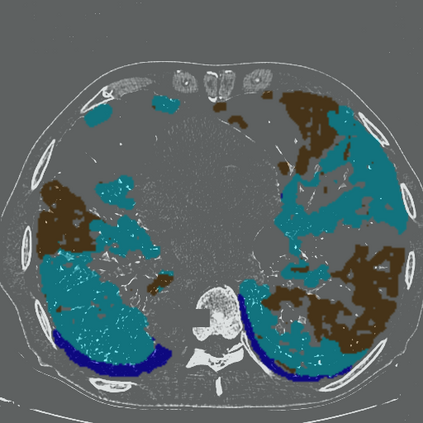

The novel coronavirus disease 2019 (COVID-19) has been spreading rapidly around the world and caused significant impact on the public health and economy. However, there is still lack of studies on effectively quantifying the lung infection caused by COVID-19. As a basic but challenging task of the diagnostic framework, segmentation plays a crucial role in accurate quantification of COVID-19 infection measured by computed tomography (CT) images. To this end, we proposed a novel deep learning algorithm for automated segmentation of multiple COVID-19 infection regions. Specifically, we use the Aggregated Residual Transformations to learn a robust and expressive feature representation and apply the soft attention mechanism to improve the capability of the model to distinguish a variety of symptoms of the COVID-19. With a public CT image dataset, we validate the efficacy of the proposed algorithm in comparison with other competing methods. Experimental results demonstrate the outstanding performance of our algorithm for automated segmentation of COVID-19 Chest CT images. Our study provides a promising deep leaning-based segmentation tool to lay a foundation to quantitative diagnosis of COVID-19 lung infection in CT images.